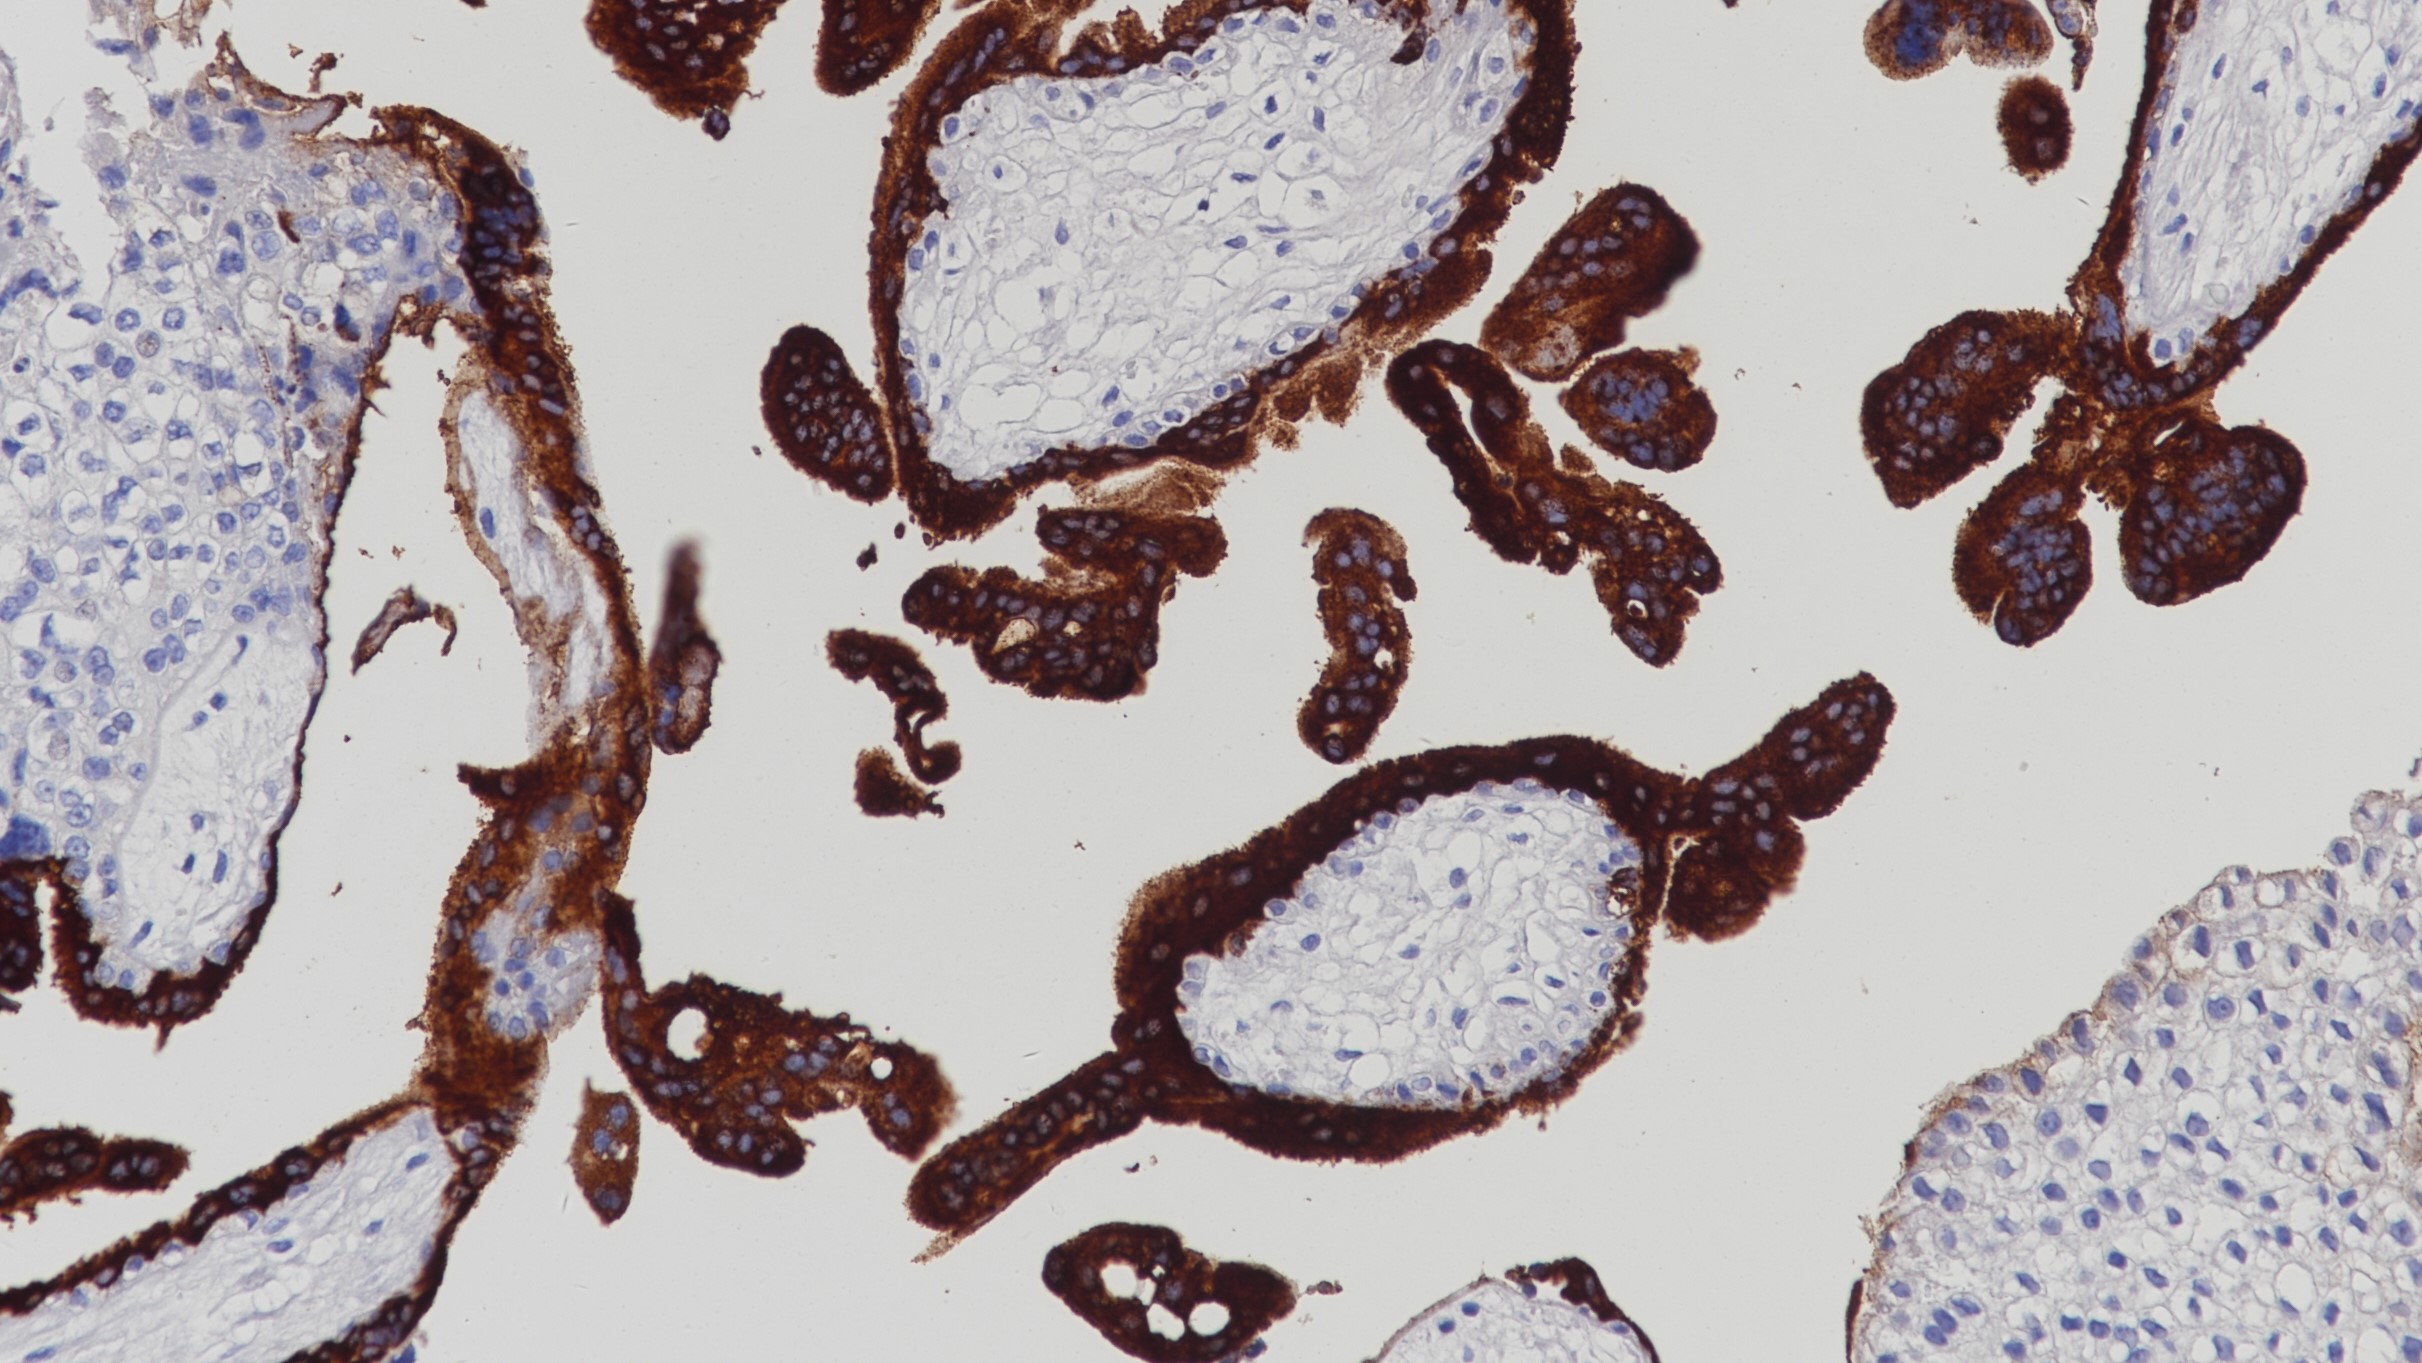

1.Singer, W, Spellacy, W.N. HUMAN PLACENTAL LACTOGEN. British Medical Journal 20 September 1969 668-669.

2.C W Welsch, M J McManus. Stimulation of DNA synthesis by human placental lactogen or insulin in organ cultures of benign human breast tumors. Cancer Research 37, 2257-2261, July 1977.